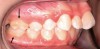

Fig 6. Patient with cleft palate treatment history and underdeveloped craniofacial growth, facial view (Fig 6) and occlusal view (Fig 7).

Figure 6

Fig 7. Patient with cleft palate treatment history and underdeveloped craniofacial growth, facial view (Fig 6) and occlusal view (Fig 7).

Figure 7

Although the face is a 3-dimensional structure, craniofacial growth modification is a topic that may be stratified by reviewing the transverse, vertical, and anterior-posterior dimensions. A transverse growth inadequacy is often illustrated in the form of a posterior (and often anterior) crossbite.21 The most common cause of this inadequacy is an underdeveloped maxilla, or, alternatively, an overdeveloped mandible; oftentimes a combination of these characteristics is the source of the problem. One example is a patient who has had cleft lip/palate repair, which may lead to craniofacial growth restriction in all dimensions (Figure 6 and Figure 7). When considering the transverse dimension, the most common treatment for a posterior crossbite is RPE therapy.21 In mild cases, archwire or dental expansion may suffice.